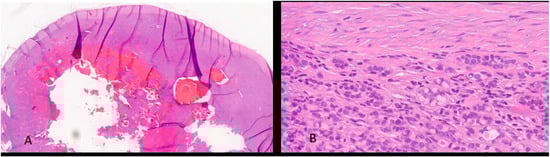

The post-operative histological examination showed the following: “a whitish nodular lesion of 2.5 × 2 × 2 cm, centrally hemorrhagic. Microscopy revealed a neoplastic tubular proliferation with scant reticular stroma with lymphoid elements in the context. Presence of neoplastic tubules with slight nuclear atypia and a continuous basal layer, with expression of cytokeratin 7, pancytokeratin, AML, S100, and CitoA. Additional morphological findings included the presence of a thick continuous capsule and PAS+ mucous secretion. DIAGNOSIS: morphological findings consistent with metastasis of low-grade epithelial-myoepithelial carcinoma” [Figure 2 and Figure 3]. The patient was referred to a tumor board but was not considered suitable for adjuvant treatment due to advanced age (83 years) and comorbidities.

Figure 2. H&E-stained section. (A) (2 HPF magnification) shows an expansive, invasive nodular neoplasia characterized by bland central necrosis and hemorrhagic areas, surrounded by a hypercellular peripheral zone. (B) (40 HPF magnification) shows some histological and cytological details of neoplasia composed of myoepithelial epithelioid, plasmacytoid or spindle cell, single or aggregate in nests, or solid and trabecular structures.